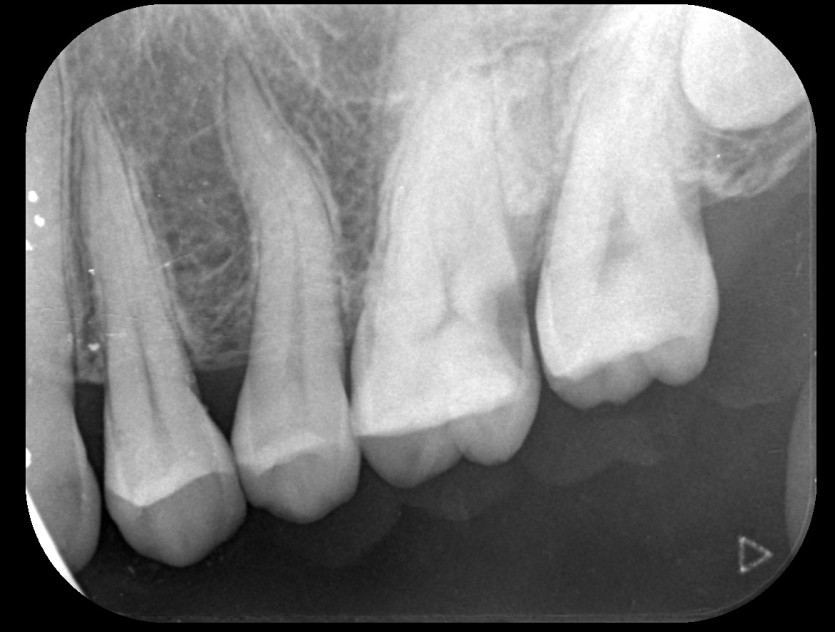

신경치료 사례